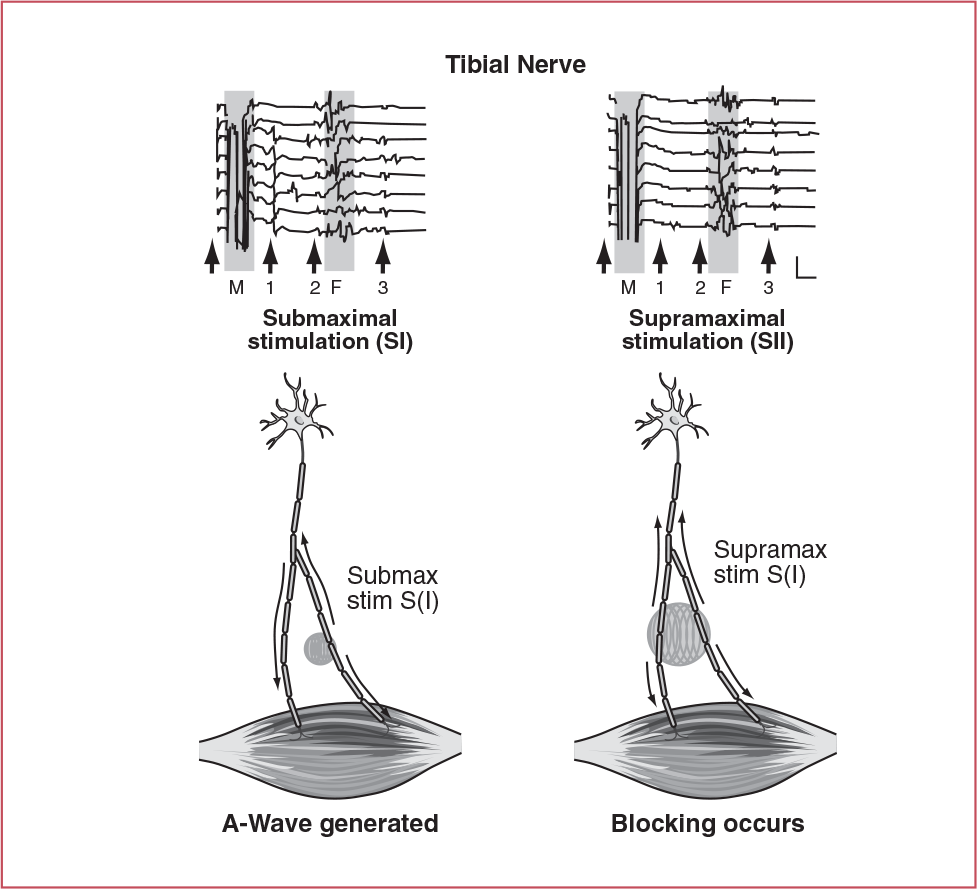

What does an A- (Axon) Wave represent?

collateral sprouting following nerve damage